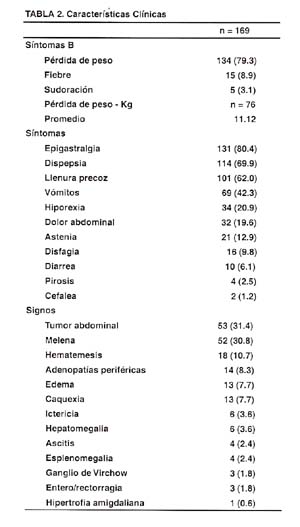

En la Tabla N° 2, se aprecia las características clínicas evaluadas en los 169 pacientes con Linfoma Gástrico. La triada de los llamados síntomas B no se manifiesta de manera característica y uniforme, presentando fiebre y sudoración menos del 9% de los pacientes, no siendo esta triada una sintomatología característica de esta enfermedad. La pérdida de peso promedio es de 11.12 Kg y lo presenta la mayoría de los pacientes (79.3%). Los síntomas más representativos son: el dolor abdominal tipo epigastralgia, la dispepsia, la llenura precoz, los vómitos y la hiporexia. En menor frecuencia de presentación están el dolor abdominal difuso, la astenia, la disfagia, la diarrea y escasamente la pirosis y la cefalea. Dentro de los signos, aquellos que tuvieron mayor frecuencia de presentación fueron: la presencia de tumor abdominal (31.4%), y de melena (30.8%), además de hematemesis (10.7%). El tumor abdominal estuvo presente en tres de dieciséis pacientes con Maltoma y en uno de cada tres pacientes con Linfoma no MALT, siendo este el signo más frecuente de presentación. Otros signos importantes en orden decreciente fueron: las adenopatías periféricas, el edema, la caquexia, la ictericia, la hepatomegalia, la ascitis y la esplenomegalia, entre otros.